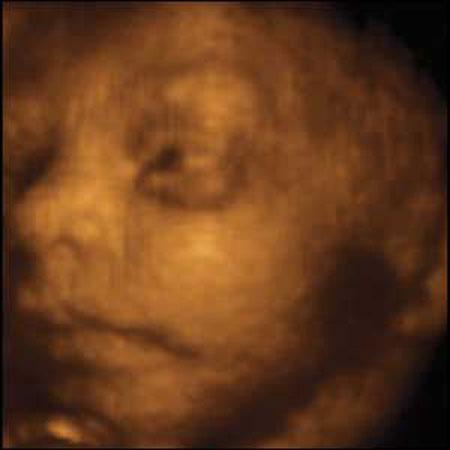

Ультразвуковые съёмки аборта на 12 неделе явно показывают: ребёнок чувствует боль, как любой из нас, и прекрасно понимает, что его хотят убить - он всеми силами старается отодвинуть от себя инструмент и широко раскрывает рот в безмолвном крике, когда у него отрывают сначала ноги, затем часть туловища…

Голову извлекают в последнюю очередь и лицо убитого ребёнка всегда искажено гримасой боли и ужаса. По этим кадрам видно, что практически нет разницы, убить ли 3-месячного ребёнка в утробе или отрезать руки -ноги -голову 5-летнему малышу. Без анестезии и в полном сознании.

- Фильм американского врача Бернарда Нэйтансона, названный «Безмолвный крик», показал всему миру, что такое аборт на сроке 11 недель беременности. Многие врачи и медсестры, посмотрев фильм, прекратили участвовать в абортах.

Это документальный фильм, и авторы рекомендуют соблюдать осторожность при его показе, поскольку некоторые кадры могут вызвать у человека психологический шок: безмолвный крик внутриутробного младенца, искаженное от боли лицо ребенка, погибающего на наших глазах...

Из закадрового текста к фильму: «Инструмент еще не коснулся ребенка, но он уже возбужден, его сердечные удары учащаются и достигают приблизительно 200 ударов в минуту. Вакуум-кюретка нащупывает ребенка, и он широко раскрывает рот в безмолвном крике».